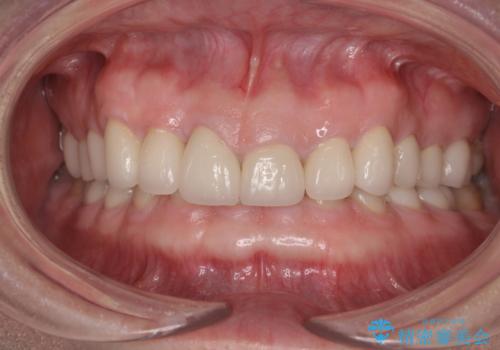

口を開けたときに見える範囲をオールセラミッククラウンとし、とても自然な口元に仕上げることができました。